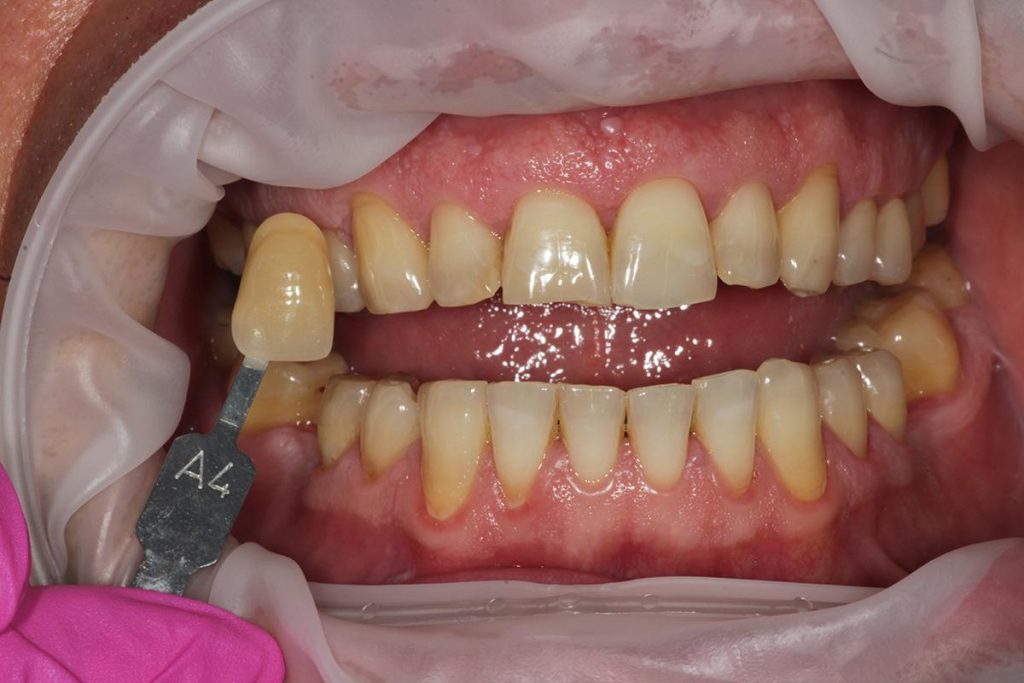

Pierwszy etap to kompleksowa konsultacja u dr Joanny Zawirskiej-Poły. Podczas tej wizyty zostało wykonane badanie przedmiotowe, podmiotowe, badanie mięśni i stawów, analiza okluzji, badanie stomatologiczne, tomografia komputerowa, rejestracja fotograficzna i długa rozmowa z Pacjentką na temat jej oczekiwań.

Pacjentka, zgłaszając się już na kolejną wizytę świadomie podjęła opcję pośrednią z proponowanych działań: wyleczenie zębów zachowawczo, endodontycznie z zabezpieczeniem protetycznym, estetyczne korekty uśmiechu licówkami, ćwierćkoronami i koronami, jednak bez pełnej przebudowy zwarcia (z zachowaniem starszych odbudów w strefach bocznych, które były wykonane na implantach w przeszłości), która jest zawsze najbardziej polecana, odtwarza prawidłowe kontakty, a także umożliwia lekarzowi i technikowi najlepsze warunki do nadania odpowiednich i harmonijnych kształtów. Te wszystkie działania chronią na przyszłość staw skroniowo-żuchwowy.

Pomimo zaleceń dr do wdrożenia również leczenia ortodontycznego, Pacjentka, znając wszystkie wady i zalety bezwzględnie zdecydowana zakamuflować stłoczenia, nieprawidłowości kontaktów, płaszczyzny zgryzowe, tylko i wyłącznie protetycznymi rozwiązaniami. Dr Joanna ustaliła z Pacjentką pod Jej wymagania wspólny plan działań. Wybierając takie rozwiązanie lekarz i laboratorium ma zawsze utrudnienie, by jaknajbardziej harmonijnie zaplanować projekt uśmiechu.